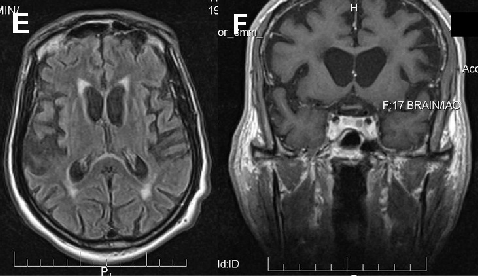

In ChAc and MLS, electroneurography may demonstrate sensorimotor axonal neuropathy whereas electromyography may show neurogenic as well as myopathic alterations. Electroencephalographic findings are not specific and may comprise normal findings, generalized slowing, focal slowing, and epileptiform discharges. Neuroradiologically, there is progressive striatal atrophy especially affecting the head of caudate nucleus and impaired striatal glucose metabolism similar to that seen in HD (Figure 2) [24,26]. Voxel-based morphometry of MRI scans in ChAc shows specific involvement of the head of the caudate nucleus [41,42]. Neurodegeneration in both core NA syndromes affects predominantly the caudate nucleus, putamen and globus pallidus. In ChAc, thalamus and substantia nigra are also involved. In contrast to HD, there is no significant cortical pathology [8,43-45]. Neuropathological findings consist of neuronal loss and gliosis of variable degree in these regions, but no inclusion bodies of any nature or other distinct neuropathological features have as yet been detected.

Cerebral MRI is often diagnostic in PKAN, and the diagnosis is confirmed by analysis of the PANK2 gene (Figure 2). Analysis of the JPH3 gene CTG expansion is useful in patients of African ancestry with suspected HDL2.

Figure 2 Neuroimaging. ChAc. Coronal FLAIR- (A) and axial T1-weighted (B) images demonstrate moderate atrophy of the caudate nucleus. MLS. Axial T2-weighted images demonstrate moderate atrophy of caudate nucleus and putamen (C) but no relevant cortical atrophy (D). HDL2. Axial FLAIR- (E) and coronal T1-weighted images (F) demonstrate atrophy of the caudate nucleus and the fronto-temporal cortex. In addition, FLAIR images show periventricular white matter hyperintensities (courtesy of Nora Chan, MD, UCLA, Los Angeles, USA). PKAN. T2-weighted fast spin echo (G) and T1-weighted (H) brain MRI scans from a child with PKAN demonstrating the “eye of the tiger” sign (courtesy of Susan J. Hayflick, MD, Oregon Health and Science University, Portland, Oregon, USA)